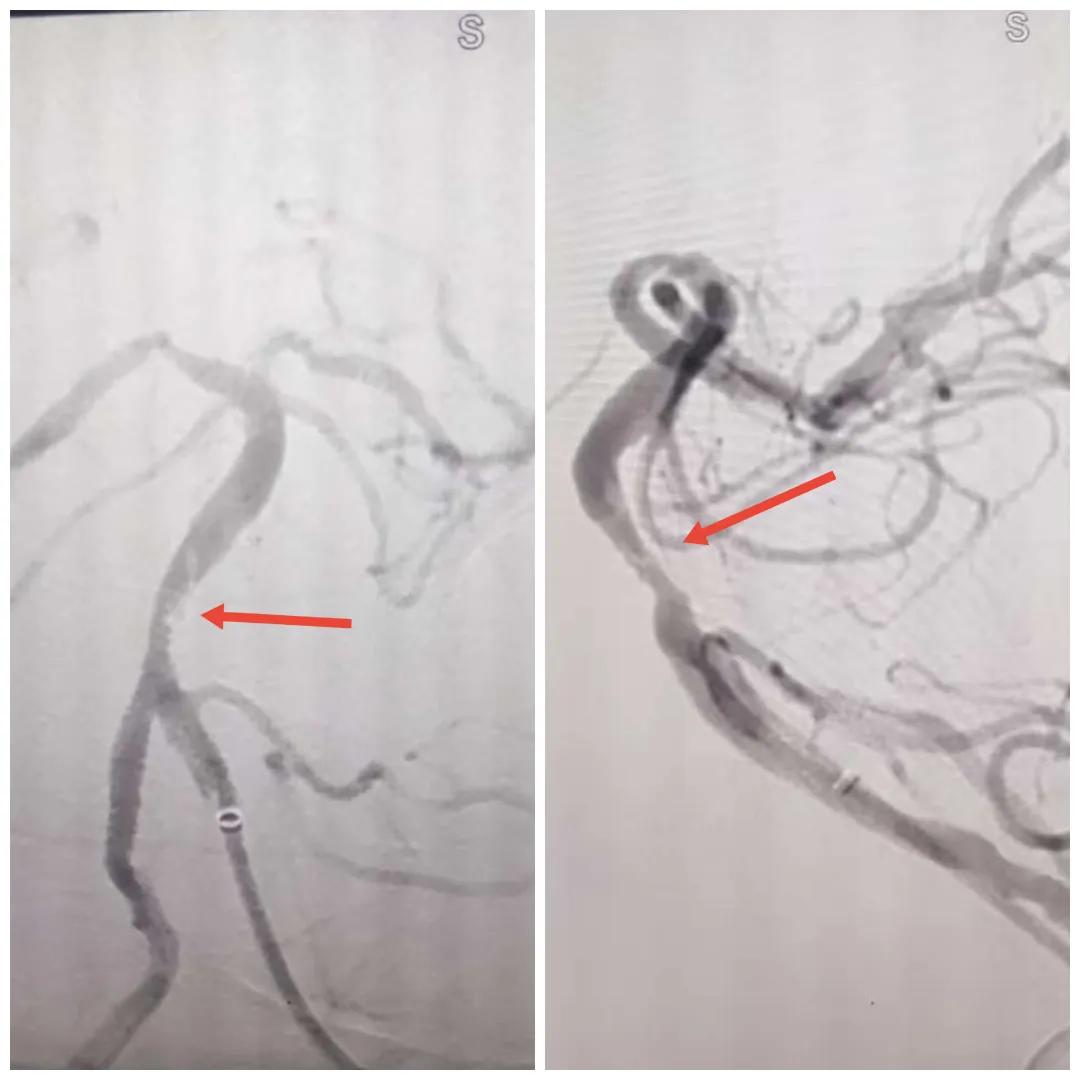

在經(jīng)造影后,主刀醫(yī)生腦一科副主任楊慶堂發(fā)現(xiàn)患者基底動(dòng)脈下段重度狹窄且狹窄段以遠(yuǎn)有大負(fù)荷血栓,其狹窄處考慮為動(dòng)脈夾層,手術(shù)難度及風(fēng)險(xiǎn)較大。楊慶堂副主任在彭壯副主任醫(yī)師的協(xié)助下運(yùn)用spaceman(太空人)技術(shù),中間導(dǎo)管抵近血栓抽吸配合支架拉栓,成功開通血管。再次造影可見基底動(dòng)脈管腔明顯增寬,遠(yuǎn)端血管顯影良好,且等待20分鐘后造影仍顯示血流通暢。楊慶堂副主任考慮到本次手術(shù)時(shí)間不宜過長,現(xiàn)患者基底動(dòng)脈及分支前向血流維持良好,給予其抗栓藥物應(yīng)用后結(jié)束手術(shù),并建議患者3個(gè)月后復(fù)查造影,明確其基底動(dòng)脈夾層情況。

取栓后血管管腔增寬,前向血流良好